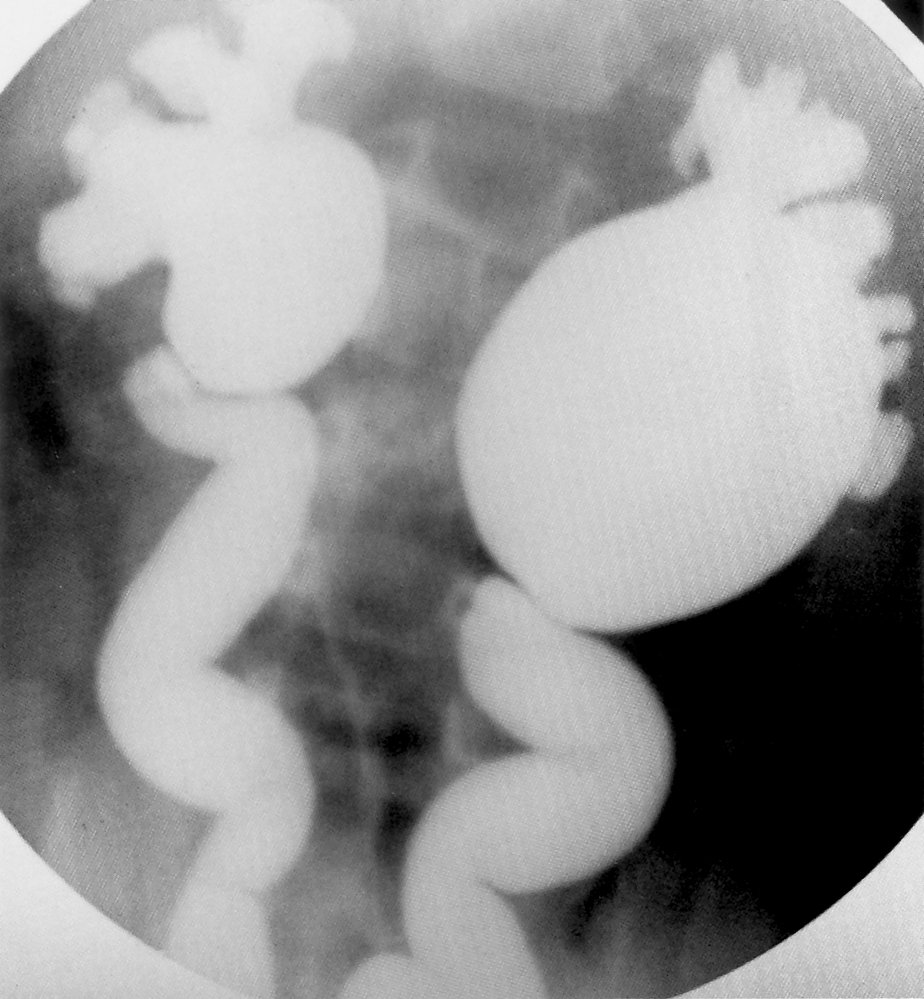

Voiding cystourethrography [2][5][14]

• Only used if there is high suspicion for VUR because of its invasive nature and use of radiation

• Potential findings include:

• Visualization of VUR (see ā€œDiagnostics of VURā€) [2][3]

• Obstructive uropathy (e.g., stenosis, hydronephrosis)